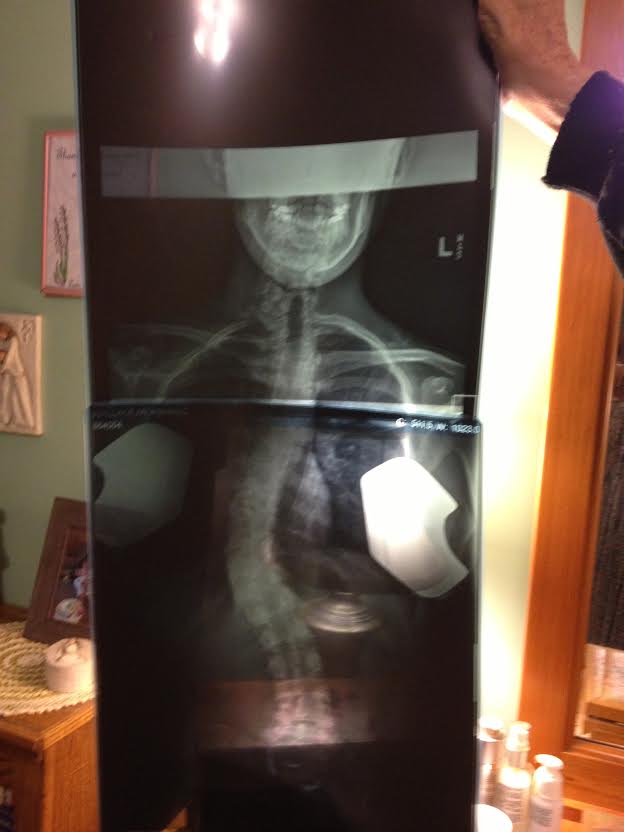

My story began when I was entering 5th grade. After the very standard scoliosis screening, I was referred to a specialist since my spine had concerning curves. As the degree of the curves progressed, I was fitted for the Boston Brace. As if the experience of middle school wasn't already awkward enough, I had to wear the brace for 23 hours a day for three years. Over the course of these three years, my curves continued to progress. Not only did my spine curve, but it was also twisting, which had the potential for some serious complications. By the time I was a freshman in high school, doctors recommended spinal fusion surgery. This was scary, very scary. Not only for me, but for my family as well. There was no one in the world who could convince my mom that her youngest daughter would be better off with a major operation leading to titanium rods and pedicel screws in her back, no one except the comforting and knowledgeable Dr. Bernard Rawlins from the Hospital for Special Surgery.

I strive to stay as healthy and active as possible. To me, it is the least I can do after being given a second chance at a healthy body. Looking at your own x-rays of 70 degree curves and being told your lung capacity will soon be affected makes scoliosis scary. HSS provided me an opportunity to exchange those x-rays for straighter ones and for that, I am eternally grateful. Although I am just one of Dr. Rawlin's thousands of patients, he will always be my number one doctor. I am thankful to him for his medical expertise, support to my family, and calming personality. He is a remarkable man who does so much for many people. He has donated a great deal of his time and resources to his home country of Ghana, so that the children their can also live happy and healthy lives. If we could all strive to adopt his giving personality, this world would be a better place! Thank you Dr. Rawlins and HSS!